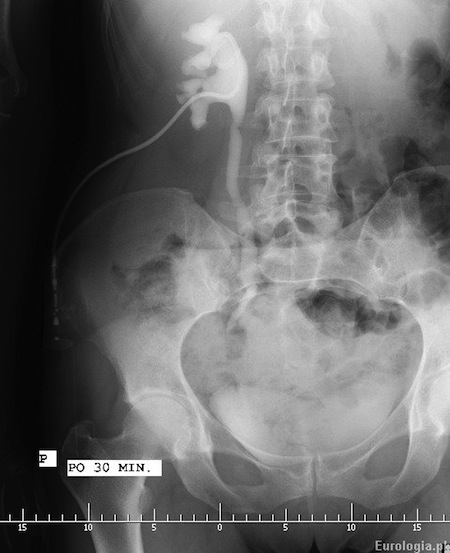

Fot. Pielografia zstępująca

Zdjęcie rentgenowskie powyżej przedstawia obraz pielografii zstępującej po 30 minutach od podania kontrastu przez dren nefrostomijny. Nefrostomia założona była około 3 tygodni wcześniej z powodu prawostronnego roponercza. Stop spływu na wysokości dolnej krawędzi stawu krzyżowo - biodrowego. Przyczyną, która spowodowała roponercze była kamica moczowodowa.